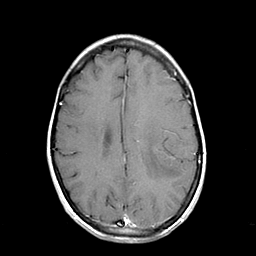

Metastatic bronchogenic carcinoma: T1-weighted MR -- Slice #15

[Home][Help][Clinical] Slice 15